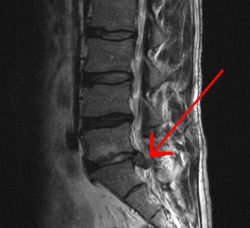

The discs are located between each boney vertebrae on the spine. The disc are flexible and allow greater movement of the spine so we can function properly. The discs are made up of a harder outer structure called the annulus. The annulus basically looks like the rings of a tree and is made of of collagen. The very centre of the disc has a soft jelly liek structure called the nucleus. It is the nucleus that bulges out or prolapses when given the opportunity. The ooprtunity arises when there are tears in the annulus or the annulus has simply stretched over time. The picture above and below show herniated discs which is the next step beyond a simple bulging disc.

Spinal disc herniation may be due to repeated microtrauma, major trauma, lifting injuries, or idiopathic (unknown) causes, in which a tear in the outer, fibrous ring (annulus fibrosus) of an intervertebral disc (discus intervertebralis) allows the soft, central portion (nucleus pulposus) to bulge out beyond the damaged outer rings. Tears are almost always postero-lateral in nature owing to the presence of the posterior longitudinal ligament in the spinal canal. This tear in the disc ring may result in the release of inflammatory chemical mediators which may directly cause severe pain, even in the absence of nerve root compression. This si known as Internal Disc Degrangement (IDD)